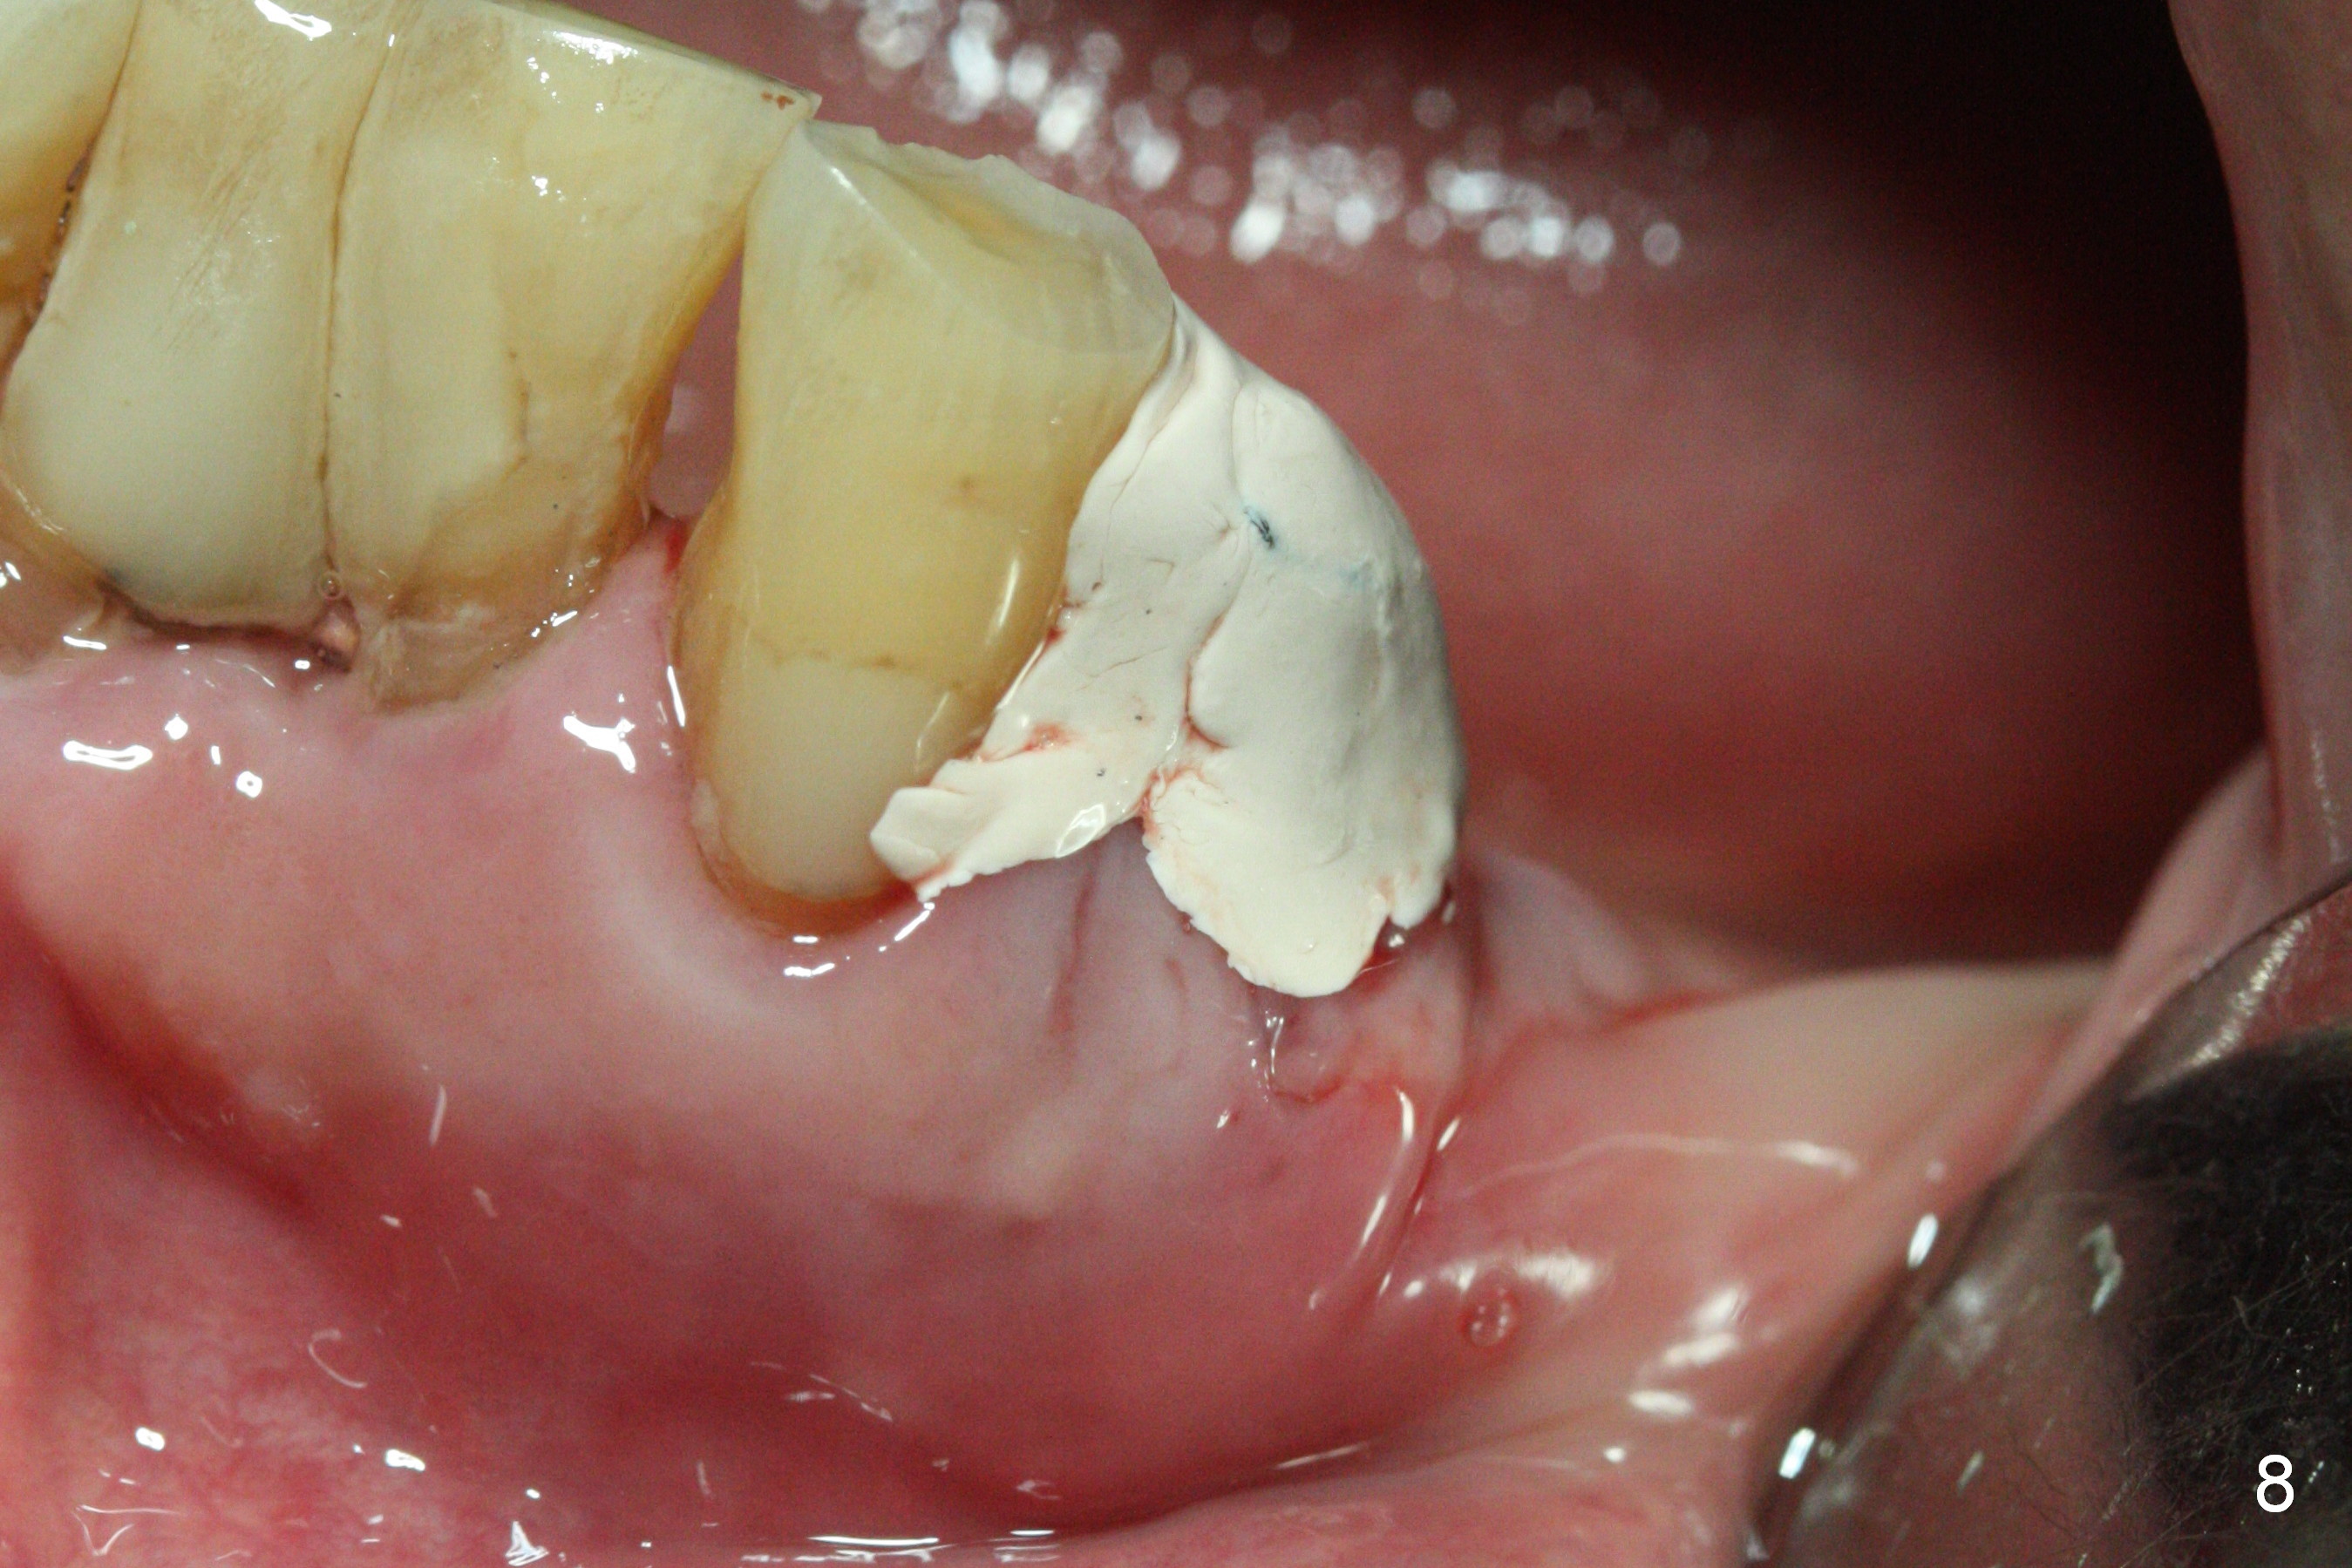

A 72-year-old man presents to clinic for implants because of pain associated with wearing the lower partial. The teeth #21, 24, 25 and 31 seem to be non-salvageable and are going to be replaced by implants so that the lower RPD can be reused (Fig.1). The edentulous ridge is atrophic (Fig.9 *). The upper complete denture appears to be functional. Since the tooth #21 is symptomatic (Fig.2) and the patient has chronic TMJ dislocation, the affected tooth is extracted first (Without antibiotic socket treatment) for immediate implant (Fig.3 (1.5 mm drill (placed more lingually)). The lower RPD is used as a surgical guide (Fig.4 (3 mm drill in place)). When a 3.8x16 mm implant is placed with bone graft (Fig.5 *), the underlying neurovascular bundle is undetected. A small field of panoramic X-ray is retaken; it seems that there is enough clearance from the Mental Foramen (Fig.2,6,7 (red dashed line)) and the Incisive Canal (pink dashed line). The implant is then placed 2 mm more apically (Fig.7) to reduce the chance of periimplantitis since the buccal plate is lost. A 5.5x5(5) mm abutment is placed (Fig.5) with more graft. The access of the abutment is left open so that a part of periodontal dressing is inserted for additional retention (Fig.8,9). The RPD is placed back for adaptation of the dressing. The patient is advised not to wear the RPD postop to reduce micromovement.

The patient returns 2 days postop because of hemorrhage (Fig.10,11 * after removal of loose periodontal dressing). Periodontal dressing is repacked (Fig.12). The hemorrhage may be due to incomplete removal of granulation tissue or invasion of the Incisive vessel intraoperatively, although there is no pain or paresthesia postop. Soft food is recommended without the upper complete denture. A provisional is fabricated (Fig.14 P) nearly 3 months postop (after changing the 5.5x5(5) mm abutment to 4.5x5(4) mm, Fig.13) when an implant is being place is #31.